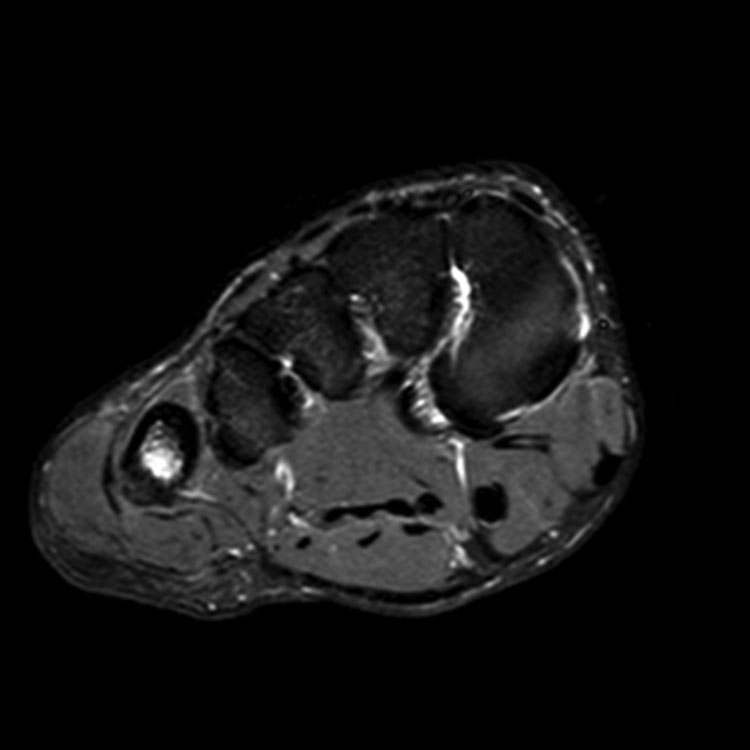

1. Accurate giagnosis 정확한 진단 : 피로반응이나 골절을 정확하게 진단하는 것이 효과적인 관리의 가장 중요한 요소.

주상골 (Navicular): 진단 및 치료가 특히 어렵습니다. 6~8주 동안 비체중 부하 깁스 고정이 치료의 선택이며, 진단이 지연된 경우에도 마찬가지입니다. 비유합, 지연 유합 또는 골절 부위의 심한 분리가 있는 경우 수술적 고정이 지시됩니다.